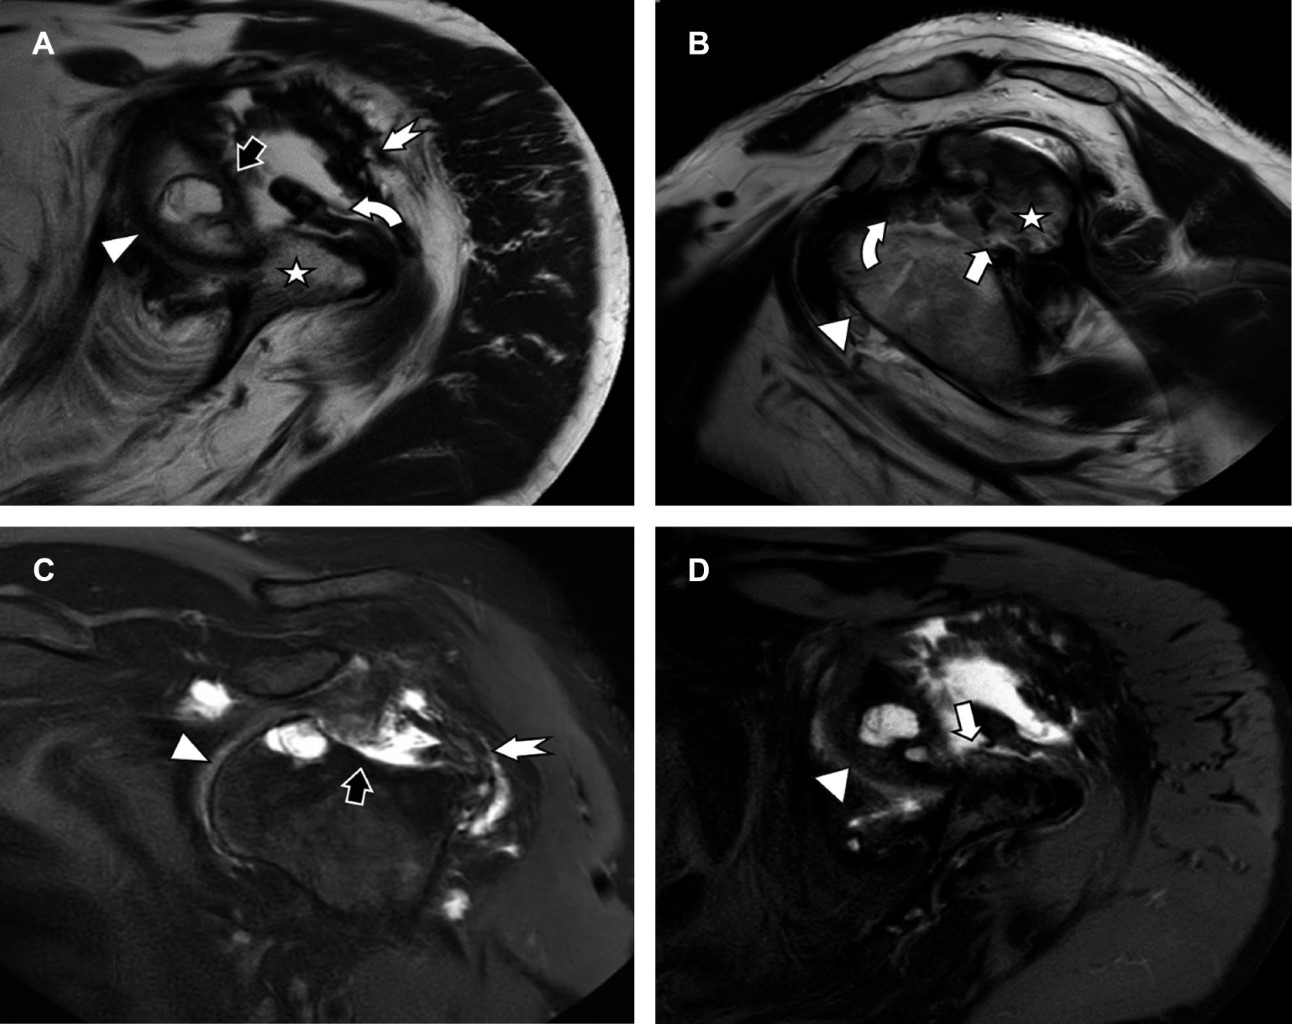

La luxación crónica de hombro es excepcionalmente rara. El abordaje terapéutico se apoya por estudios de imagen seccional. Informamos el caso de un hombre de 59 años con una luxación anterior de hombro izquierdo de más de dos años de evolución, quien desconocía su condición. Acudió a la realización de resonancia magnética (RM) como abordaje diagnóstico por limitación funcional, donde observamos la luxación anterior de hombro, con pérdida completa del cartílago articular, lesión de Bankart, lesión de Hill-Sachs, con un defecto de la cabeza humeral superior a 40%, fibrosis con engrosamiento de la cápsula articular e integridad de la porción larga del bíceps, así como del manguito rotador, a excepción del infraespinoso.

Hombre de 59 años que acude para la realización de una resonancia magnética (RM) de hombro izquierdo debido a una limitación funcional presente de más de dos años, asociada con una caída desde su propia altura, en la cual su hueco axilar quedó atrapado en el respaldo de una silla. El paciente pospuso la atención médica debido a la pandemia y a que las molestias eran tolerables. La RM revela: luxación anterior de hombro con pérdida completa del cartílago articular, lesión de Bankart, lesión de Hill-Sachs, con un defecto de la cabeza humeral que supera el 40%, fibrosis extensa con engrosamiento de la cápsula articular e integridad de la porción larga del bíceps, así como del manguito rotador, a excepción del infraespinoso (Figuras 1 y 2).

Figura 1